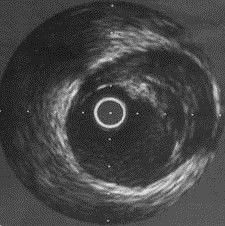

血管內超聲是利用導管將一高頻微型超聲探頭導入血管腔內進行探測,再經電子成像系統來顯示心血管組織結構和幾何形態的微細解剖信息。由於超聲探頭直接置於血管腔內探測,因此,血管內超聲不僅可準確測量管腔及粥樣斑塊或纖維斑塊的大小,更重要的是它可提供粥樣斑塊的大體組織信息,在顯示因介入治療所致的複雜的病變形態時明顯優於造影。